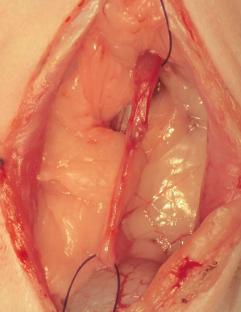

尿管移設